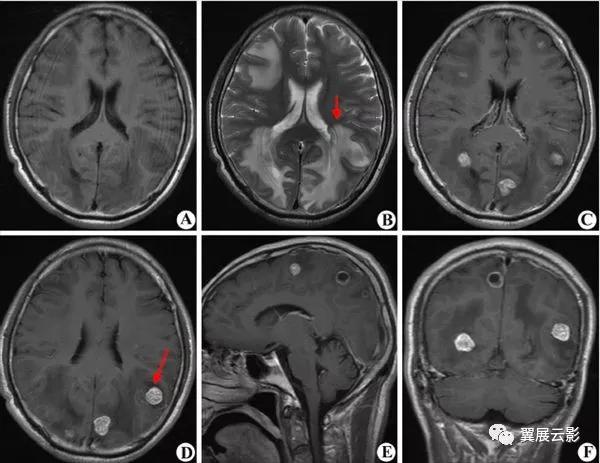

病例3:多发腔隙性脑梗死

腔隙性脑梗死为深部脑组织的小面积梗死,好发部位为基底节,丘脑,脑干,小脑及脑室旁白质区。应写清病灶的部位,大小,数目,鉴别诊断时应注意与脑血管周围腔隙相鉴别。